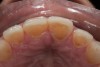

Fig 3. Preoperative view showing erosion of palatal surfaces of upper anteriors.

Figure 3

A 40-year-old female patient complained of short teeth and asked for various options to improve her smile. On clinical examination, the palatal surfaces of the maxillary anterior teeth were found to be eroded, with the residual tooth structure having a smooth and shiny appearance (Figure 1 through Figure 3). In MIP, no restorative space was available, as the lower anterior teeth fit tightly into the upper palatal surfaces, making this a clinically challenging situation to treat conservatively. In most cases of conventional treatment protocols, such upper teeth are devitalized and restored with crowns that structurally leave the teeth in a compromised condition.10